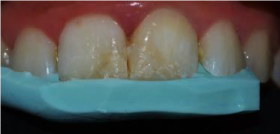

After rubber dam isolation and removing of the old restorations, a concave bevel was made on the enamel of the fracture area with the aid of a flame-shape Diamond bur (figure 4c).

Figure 4c. concave bevel on the enamel of the fracture area